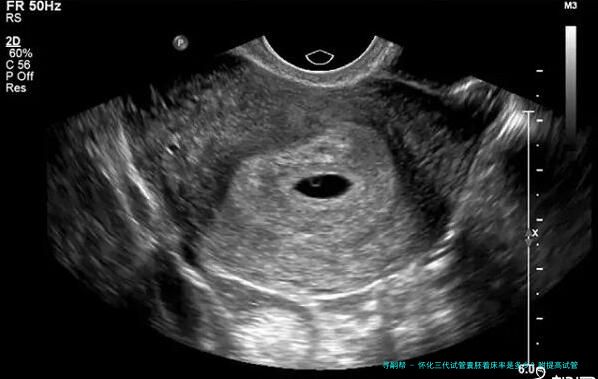

怀化三代试管 囊胚着床率是多少?

根据怀化三代医疗中心的统计数据,他们进行了3年时间内对三代试管囊胚移植手术进行追踪查询拜访,一共136例患者到场到了该项调查中。结果显示,136例患者在进行第一位次移植时,总体着床率为61.8%。